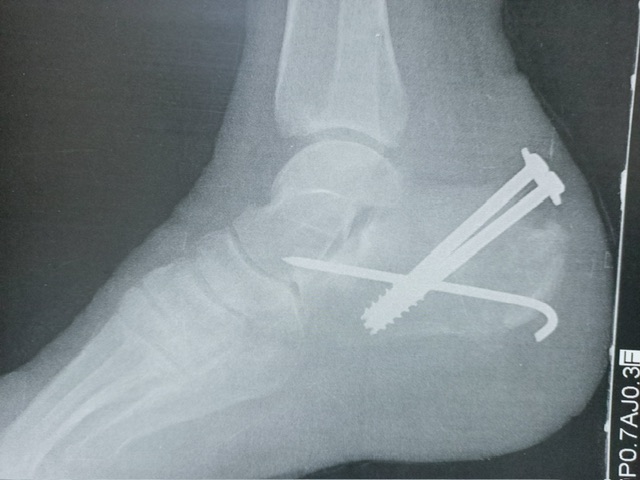

واستقبلت طوارئ مستشفى حورس التخصصي بأرمنت غرب مدينة الأقصر، ضحيتي حادثي الدهس، مصابين بتهتك في أنسجة الكاحل والعضلات مع قطع في الوتر وتفتت وكسور متعددة بالقدم والكاحل.

واتخذ الفريق الطبي لجراحة وتشوهات العظام بالتعاون مع فريق التجميل وجراحة الأوعية الدموية والتخدير والأشعة والمعمل بالمستشفى قرارهم بالتدخل الجراحي العاجل، والذي تطلب إجراء أكثر من 4 عمليات جراحة وتجميل على مدار ما يقرب من شهرين متتاليين لتثبيت عظام القدم والعصب، بالإضافة إلى عمليات بناء الأوتار والأوعية الدموية وكذلك معالجة بناء الأنسجة المحيطة، كما تم تثبيت الكسور وتغطية العظام برقع عضلية وجلدية.